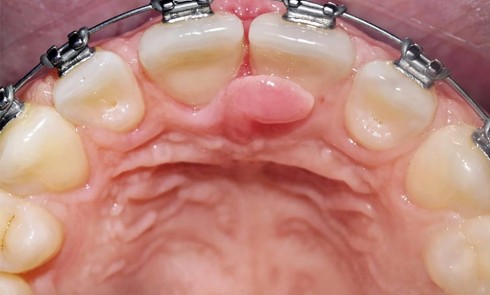

Article réservé à nos abonnés Gestion d’une complication parodontale dans un contexte de fermeture orthodontique d’un diastème interincisif maxillaire

Classification des freins interincisifs Bien qu’ancienne, la classification de Placek [Mirko et al. 1974, 1] reste d’actualité, car elle est...